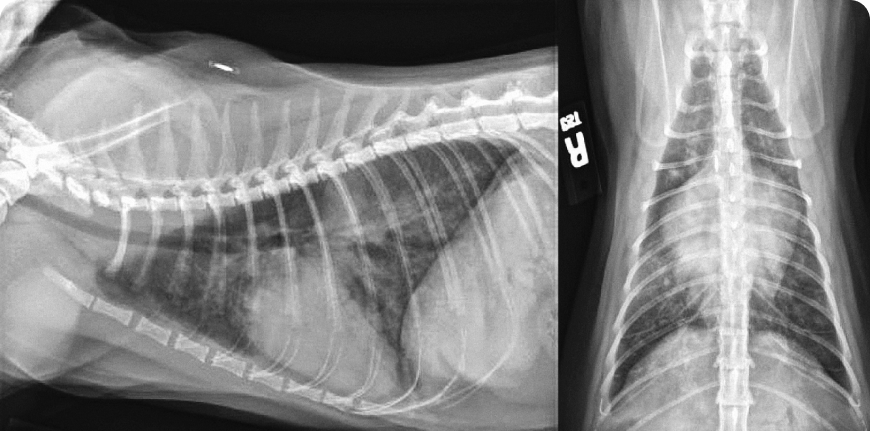

У котят шумы в сердце обнаруживают относительно часто, и при их диагностике и лечении врач должен придерживаться систематического подхода. Решающую роль в определении следующих шагов играют тщательный сбор анамнеза и тщательное клиническое обследование. Рентгенография грудной клетки может быть полезна при первоначальном обследовании, но для установления окончательного диагноза причин шума требуется эхокардиография; показанием к ее проведению считают шумы IV степени или выше, либо клинические признаки по результатам физикального осмотра. Терапию определяют исключительно на основании окончательного диагноза.